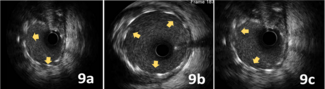

The authors compared the administered contrast volume for optical coherence tomography (OCT) imaging, the length of clear OCT images, and the immediate electrocardiographic changes following contrast injection between iso-osmolar contrast...

The authors compared the...